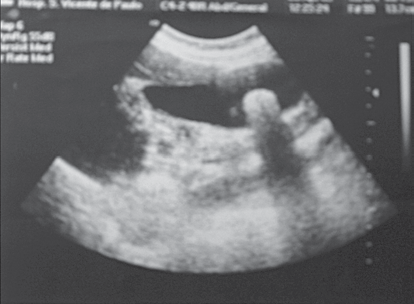

Observe a imagem.

Paciente masculino, 36 anos, apresenta o exame mostrado na imagem.

O tratamento cirúrgico está indicado pela maior possibilidade de